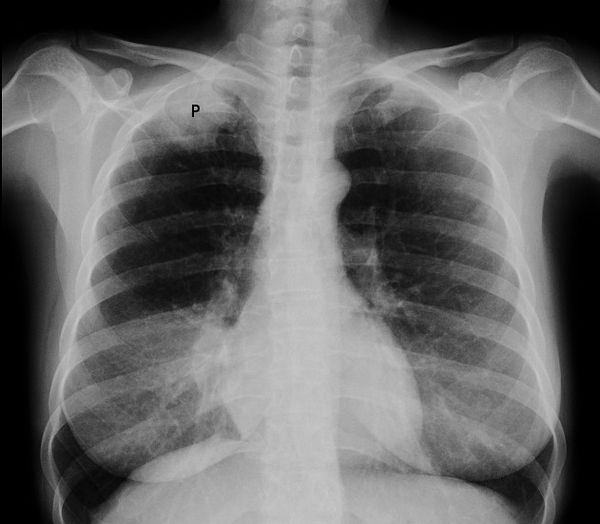

X-rays function by passing radiation through the body, which is absorbed differently by various tissues. Dense structures like bones appear white on x-ray images, while softer tissues show up in shades of gray. Air-filled spaces, such as the lungs, appear black. This contrast allows radiologists to identify abnormalities that may indicate the presence of tumors or other health issues.

Are x-rays capable of showing all types of tumors? The answer is no. X-rays are most effective at detecting tumors in certain parts of the body, particularly those surrounded by air or those affecting bone structure. However, they have limitations when it comes to soft tissue tumors.

- Lung tumors: X-rays are particularly useful for detecting lung tumors due to the contrast between the air-filled lungs and the denser tumor tissue.

- Soft tissue tumors: These are generally more challenging to detect with x-rays alone, as they may not provide sufficient contrast against surrounding tissues.

The shadow-like images on an x-ray are made from radiation being absorbed differently by different body tissues. Bones absorb the most radiation and appear white. Fat and other soft tissues absorb less radiation and appear in various shades of grey. Air absorbs the least radiation and structures filled with air (such as the lungs) appear black.

X-rays can be used to look for and examine some types of tumours. Most tumours are soft tissue and do not show up well on x-ray. Lung tumours show up well because of the air around them in the lungs.

An x-ray cannot always show the difference between a cancerous (malignant) tumour and a non-cancerous (benign) tumour.

Dense tissues such as bones block most radiation, but soft tissues, like fat or muscle, block less. After passing through the body, the beam hits a piece of film or a special detector. Tissues that block high amounts of radiation, such as bone, show up as white areas on a black background. Soft tissues block less radiation and show up in shades of gray. Organs that are mostly air (such as the lungs) normally look black. Tumors are usually denser than the tissue around them, so they often show up as lighter shades of gray.